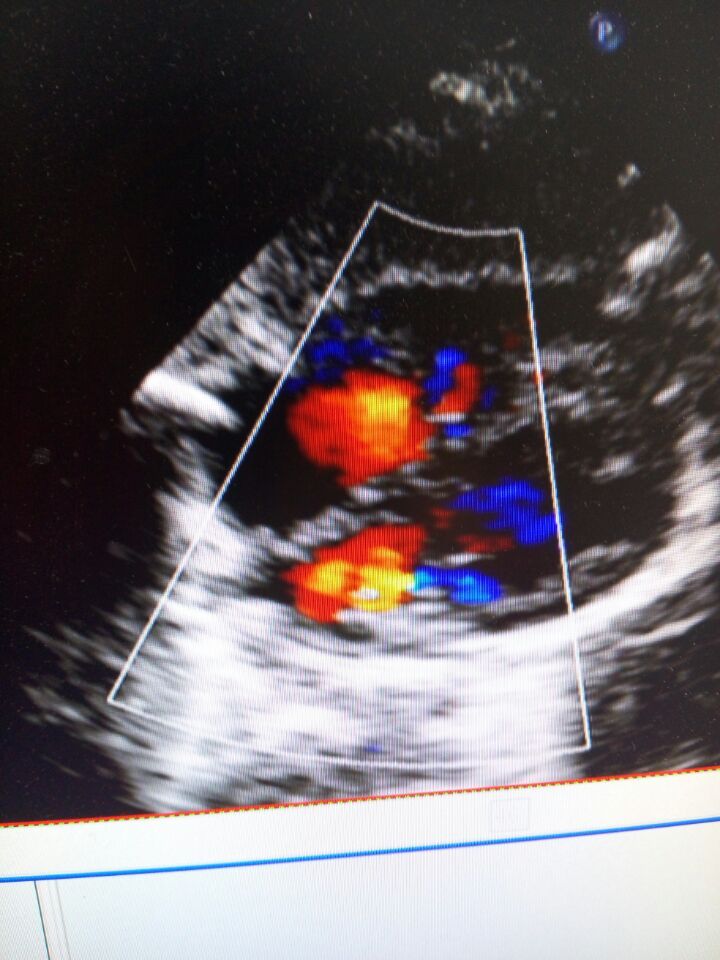

平时哭出现紫绀,没力气吃奶,易出现喉响、出汗,活动是明显,去医院做了B超肺动脉狭窄厉害才约0.3cm,主动脉骑跨约50%,室缺1.7cm,右室大,悲伤至极,想问问专家现在能手术吗?想去上海儿童医学中心手术?但农村的没出过门,希望得到好心人帮助